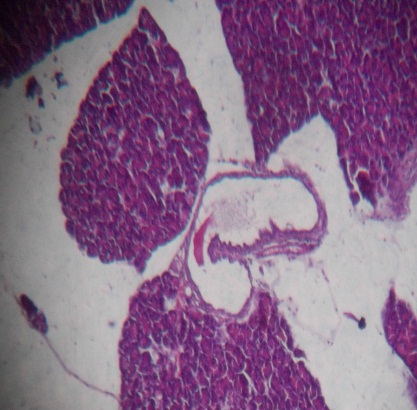

The bone marrow of Rasa Mezhugu treated rats (high/low/Middle dose) found within the central cavities of with hematopoietic tissue islands and adipose cells surrounded by vascular sinuses interspersed within a meshwork of bone (fig. 8-10). The cerebrum showed the absence of neuronal degeneration, edema and gliosis (fig. 11-13). The Cardiac muscle revealed normal appearances of the centrally arranged nucleus, connective tissue with distinct cardiac muscle fibers were well arranged (fig. 14-16). The kidney shows no glomerular or vascular injury the bowman's capsule with distinct polymorphonuclear cell nuclei with normal cells of renal cortex (fig. 17-19). The liver cells showed the normal microscopic architecture of the liver with hexagonal lobules and acini with the distinct central vein, portal triad, portal vein and hepatic artery with parenchyma cells (fig. 20-22). The lungs photos revealed that normal cytoarchitectural with predominant smooth muscle layer of the bronchi with enlargement of the alveoli and the alveoli sacs (fig. 23-25). The pancreas with normal acinar cells arranged in lobules with prominent nuclei. The islet cells are embedded within the acinar cells and surrounded by a fine capsule with normal histological structure (fig. 26-28). The spleen showed no changes congestion, hemorrhage, edema, and erosions the cells are a clear and proper arrangement (fig. 29-31). Photomicrograph of stomach mucosal layer has shown normal cells with distinct mucosa, submucosa, muscle layers and serosal layers showing normal architecture (fig. 32-34). The tests of rat’s revealed normal architecture with normal germinal epithelium, fully mature sperms filled the lumen of seminiferous tubules with tubular epithelium cells, absences of vascular congestion/interstitial edema and degenerated cells (fig. 35-37).

| Fig. 13: Histopathology slide photos of Rasa Mezhugu-High dose treated animals’ kidney | Fig. 14: Histopathology slide photos of Rasa Mezhugu-low dose treated animals’ kidney | Fig. 15: Histopathology slide photos of Rasa Mezhugu-Middle dose treated animals’ kidney |

| Fig. 16: Histopathology slide photos of Rasa Mezhugu-High dose treated animals’ Liver | Fig. 17: Histopathology slide photos of Rasa Mezhugu-Low dose treated animals’ Liver | Fig. 18: Histopathology slide photos of Rasa Mezhugu-Middle dose treated animals’ Liver |